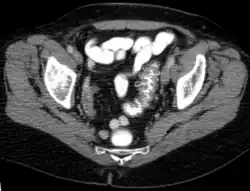

Sigmadivertikulitis mit Perforation und kleinem Abszess